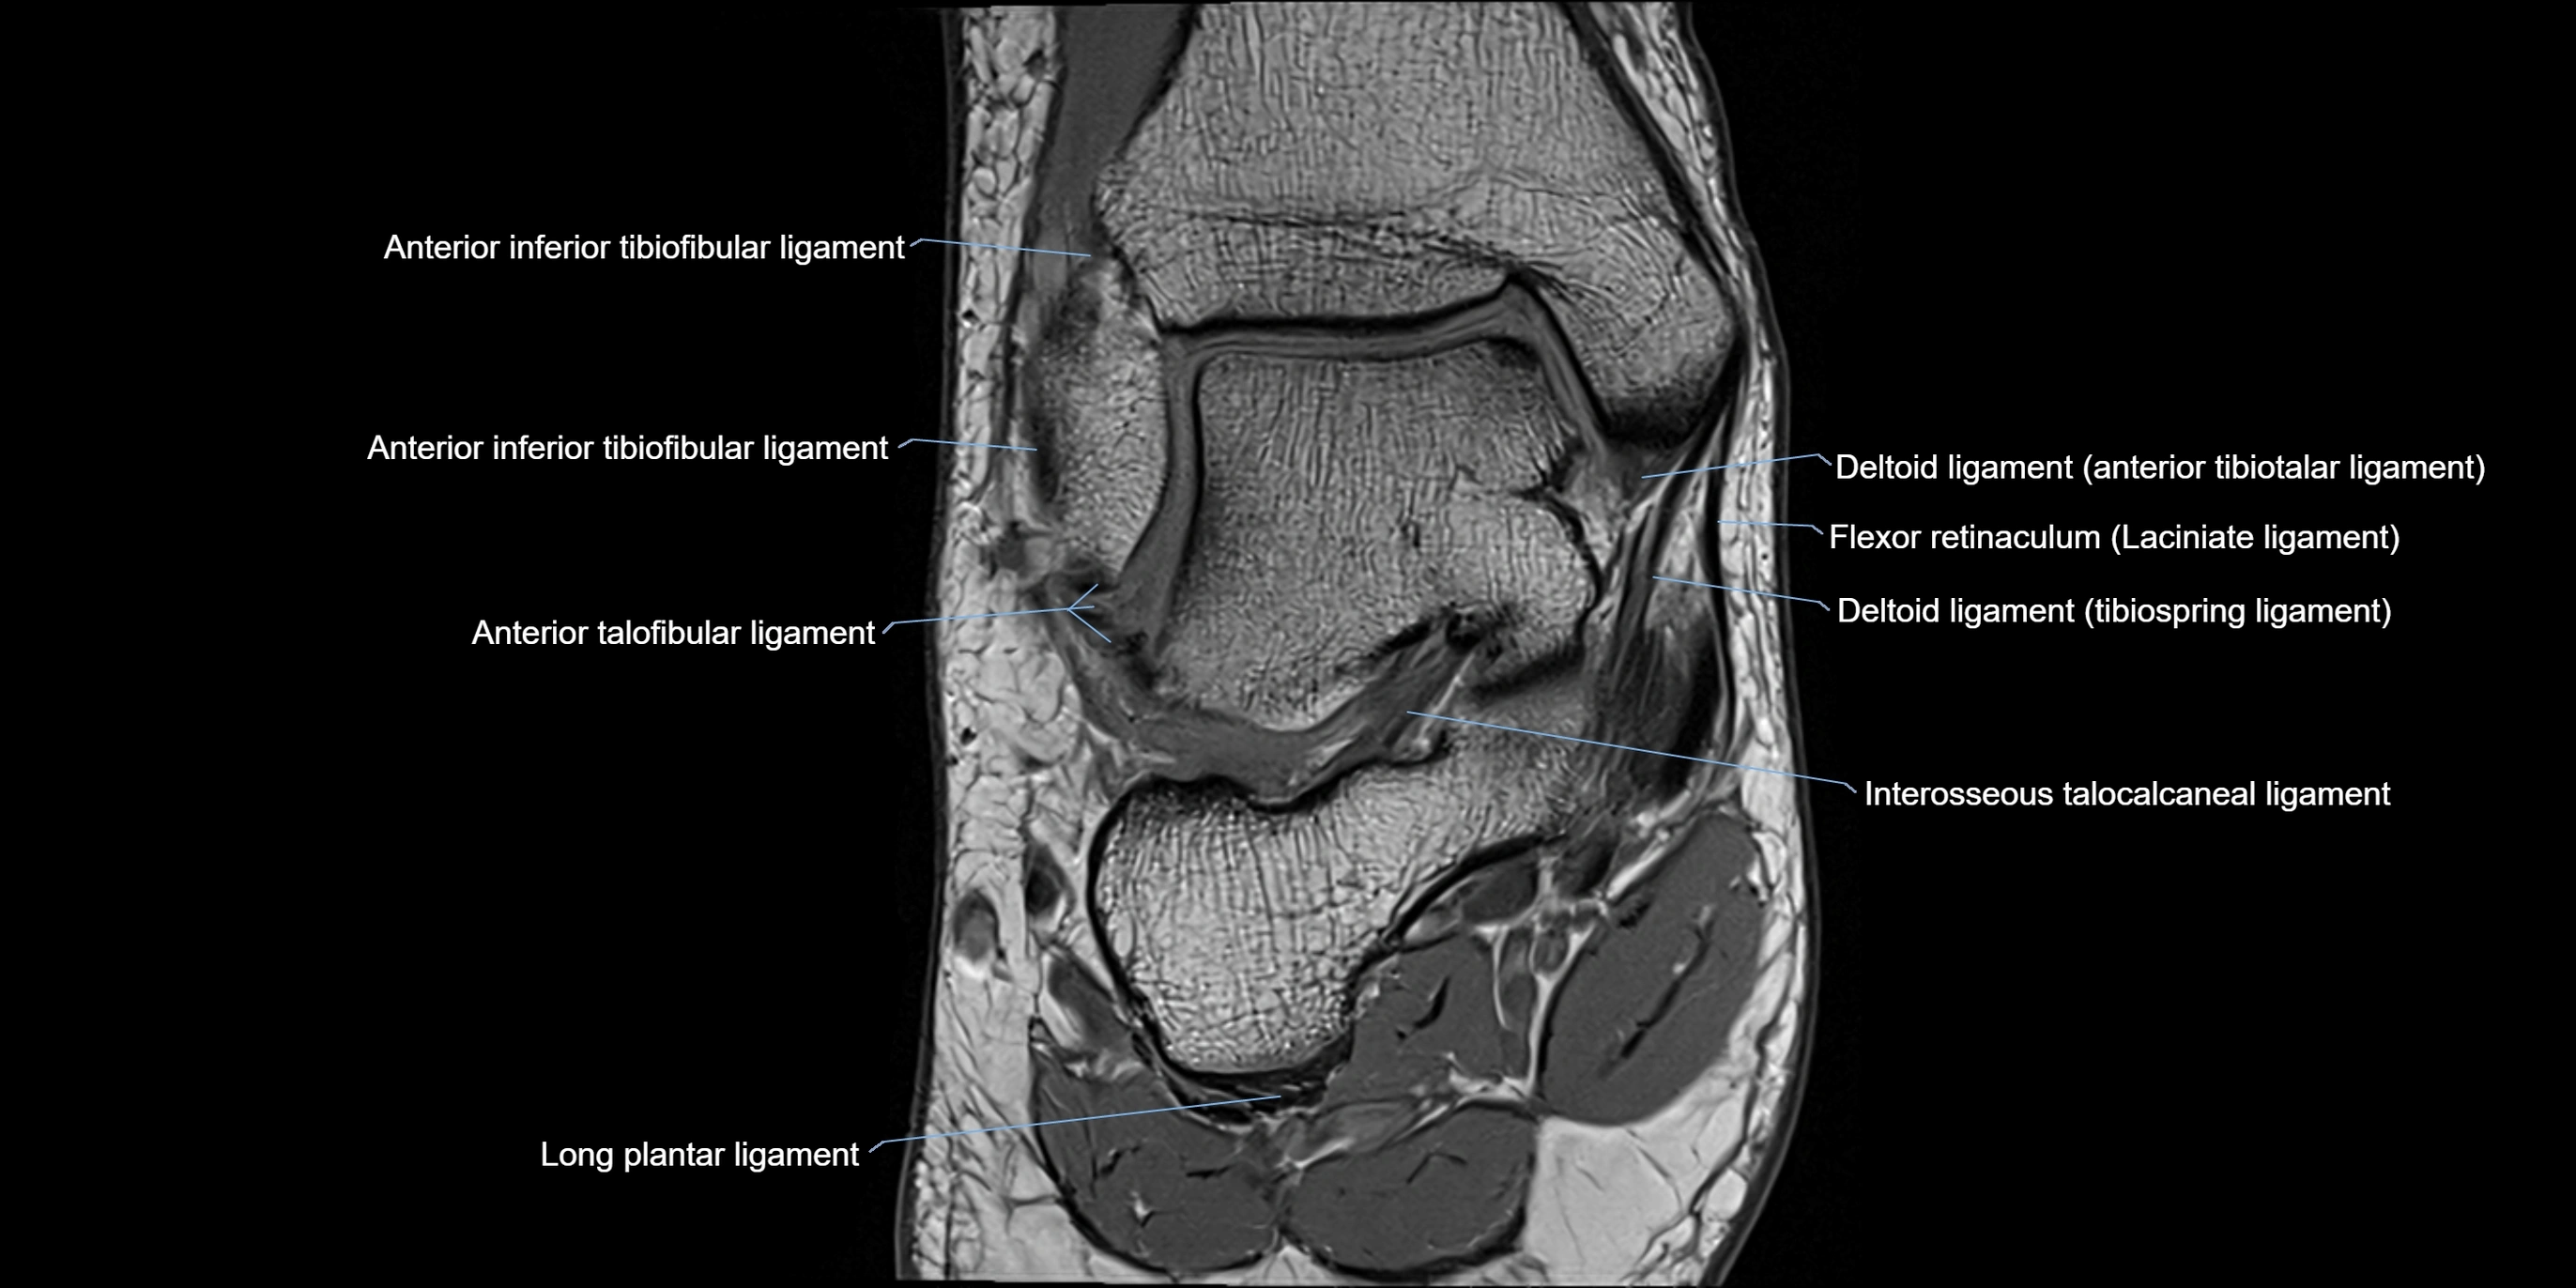

MRI image

image